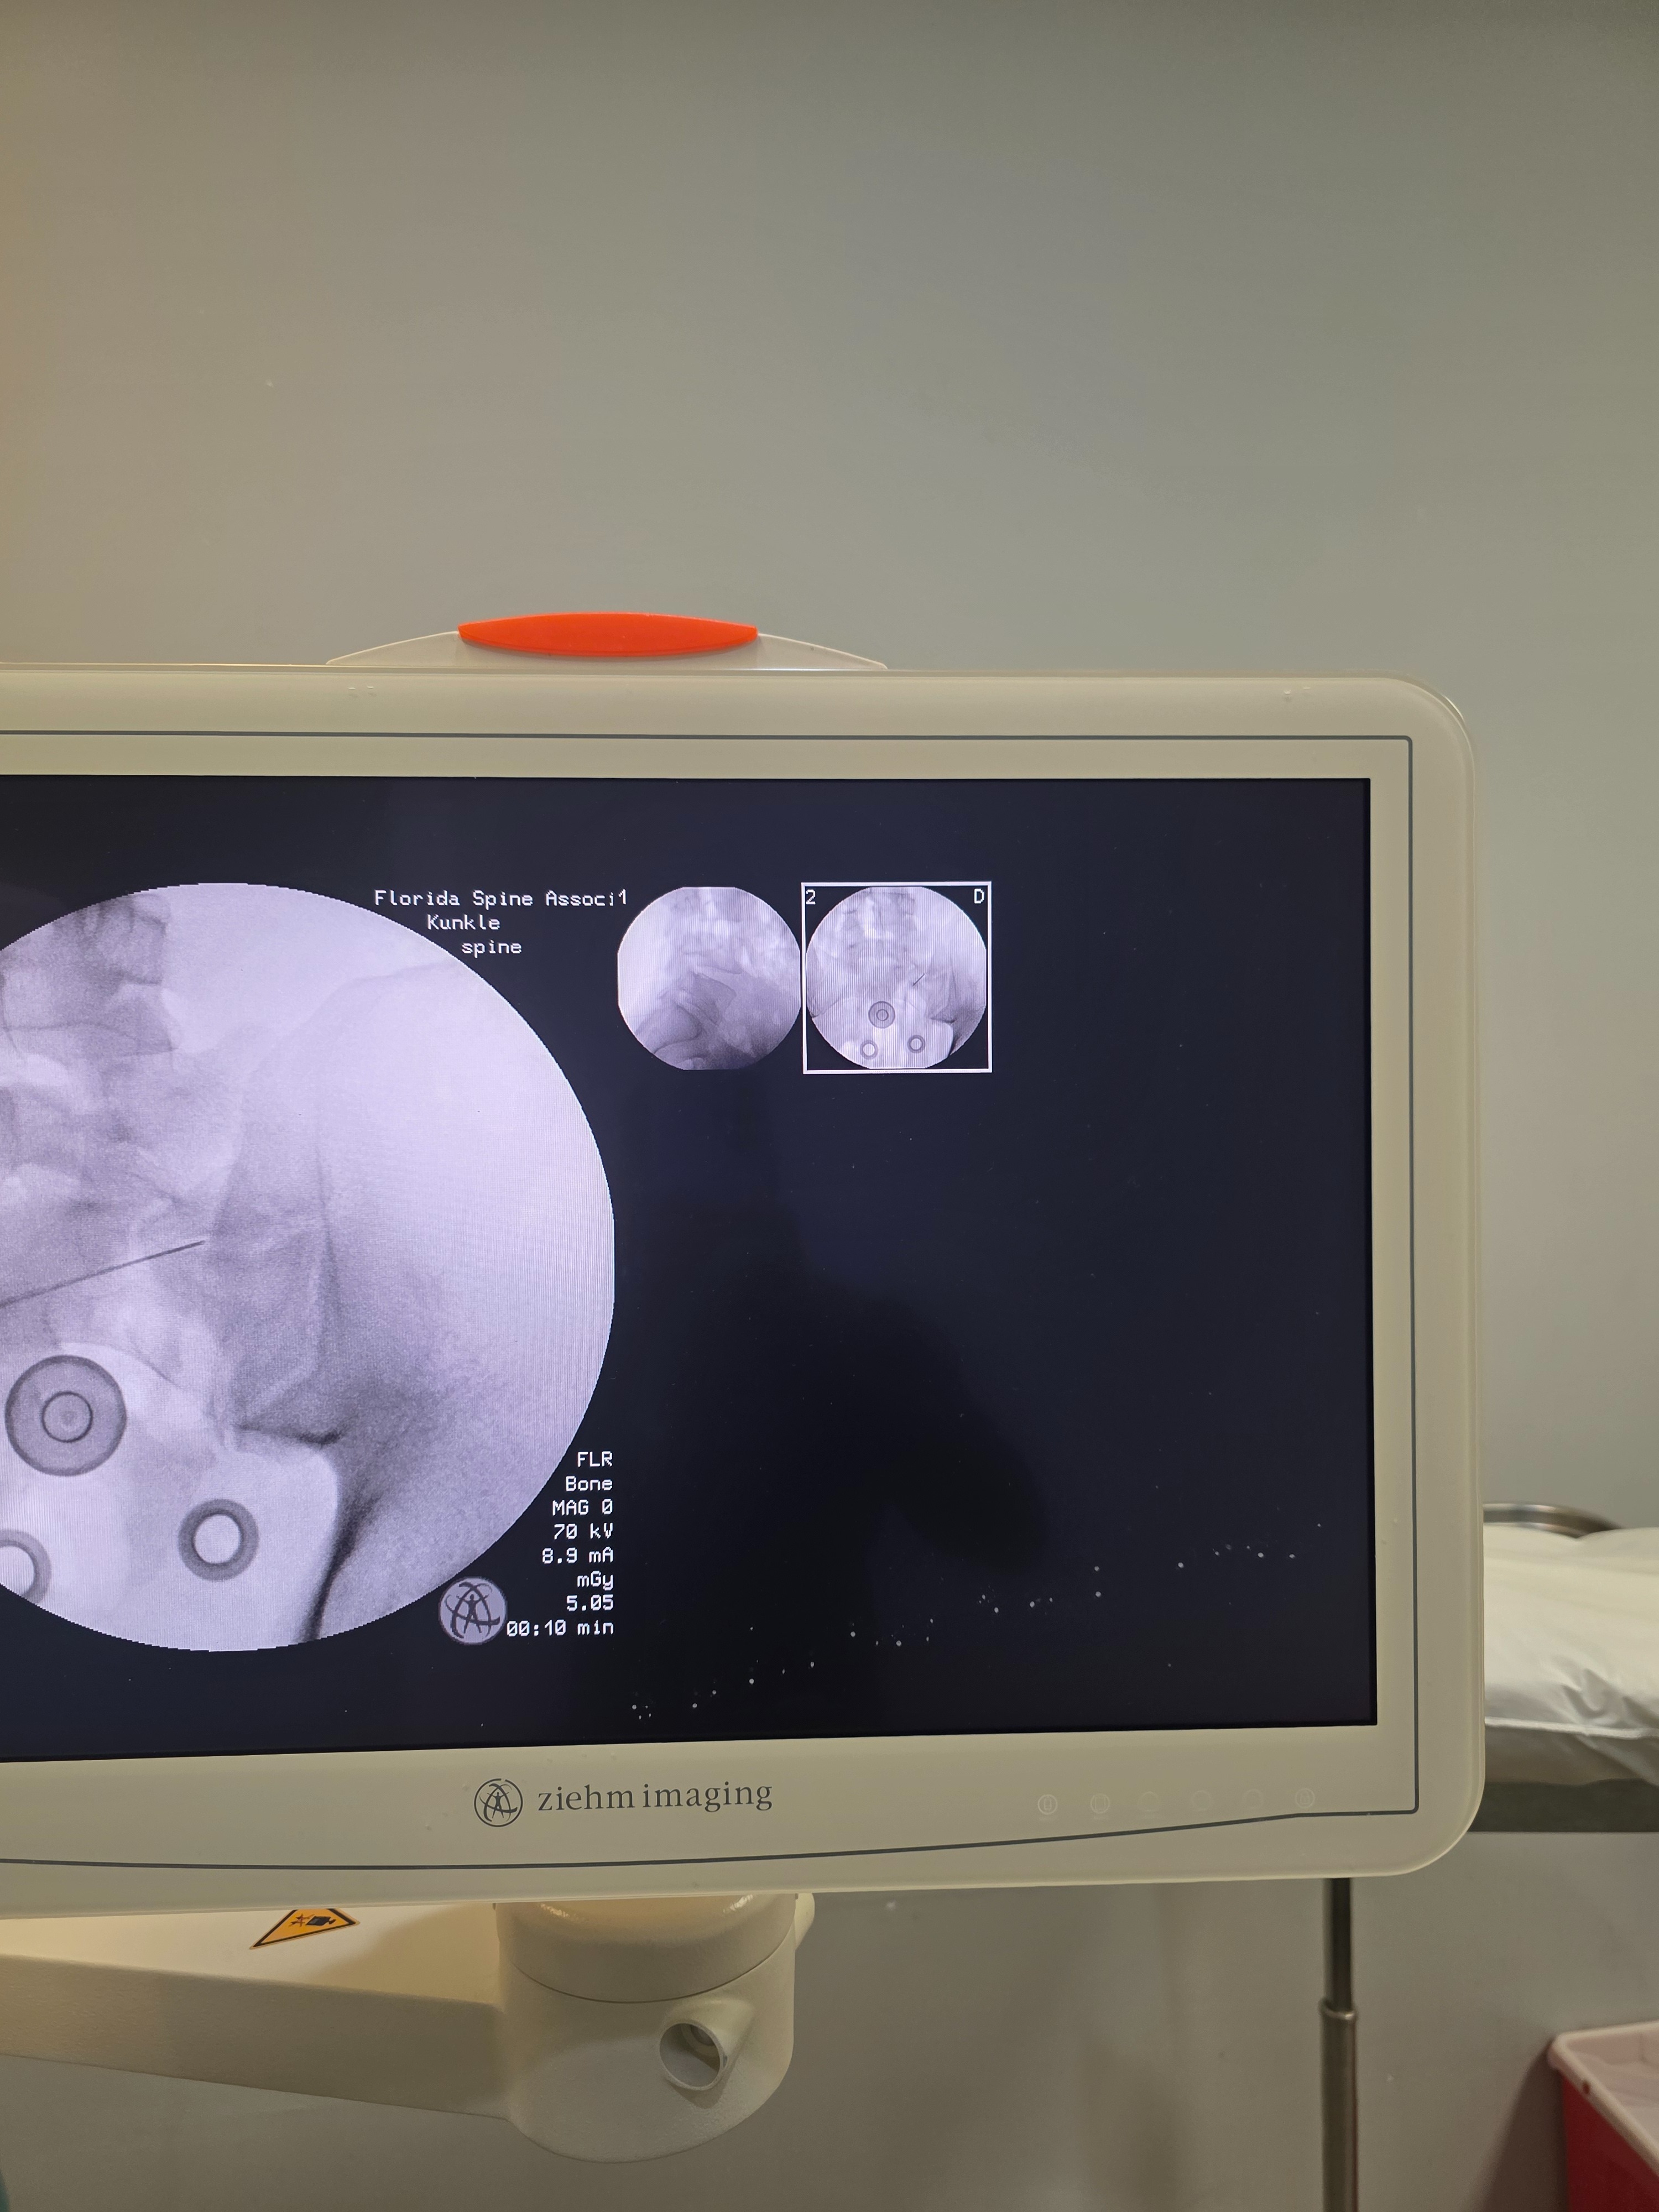

James has been battling severe lower back pain from an L5-S1 disc tear pressing on his S1 nerve, leaving him unable to work proficiently or live without pain. Surgery is his only hope for relief and recovery. Insurance will not cover all the cost. Doctors gave him too many epidural injections which caused bone density to become at -2.5(osteopenia) therefore he cannot get a disc replacement, only laser disc surgery & the medication he has been taking is affecting his kidneys and liver. Your support can help him walk freely again and rebuild his life without constant suffering.